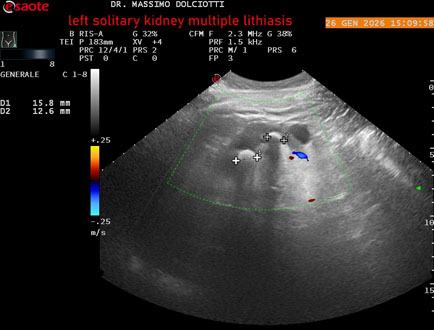

Data inserimento: 29/01/2026

Ecografia del: 26/01/2025

Strumento: Esaote MyLab Eight

Sonda: Conevx Multifrequenza 1-8 MHz

Età Paziente: M 78 anni

Motivazione dell'esame: follow up di litiasi al rene sinistro, in paziente sottoposto a nefrectomia destra.

Commento all'esame: le immagini ed il video documentano il rene sinistro in sede, di ecostruttura disomogenea per evidenza di multiple formazioni litiasiche al pielone superiore, delle dimensioni di 15,9 mm, al pielone medio di 17,5 mm e al pielone inferiore di 18,9 mm e morfovolumetria normale, con diametro bipolare di 115 (v.n. 90-120 mm) x 54 mm e parenchima renale dello spessore di 17 mm ( v.n. > 13 mm).

Conclusioni: litiasi multipla del monorene sinistro (multiple lithiasis of the left solitary kidney).

In collaborazione: Dr.ssa Marica Manfredi - Ancona, Dr. Ilir Qose - Ancona

Presentazione: Dr. Massimo Dolciotti - Ancona

Elaborazione digitale: Andrea Dini - Ancona